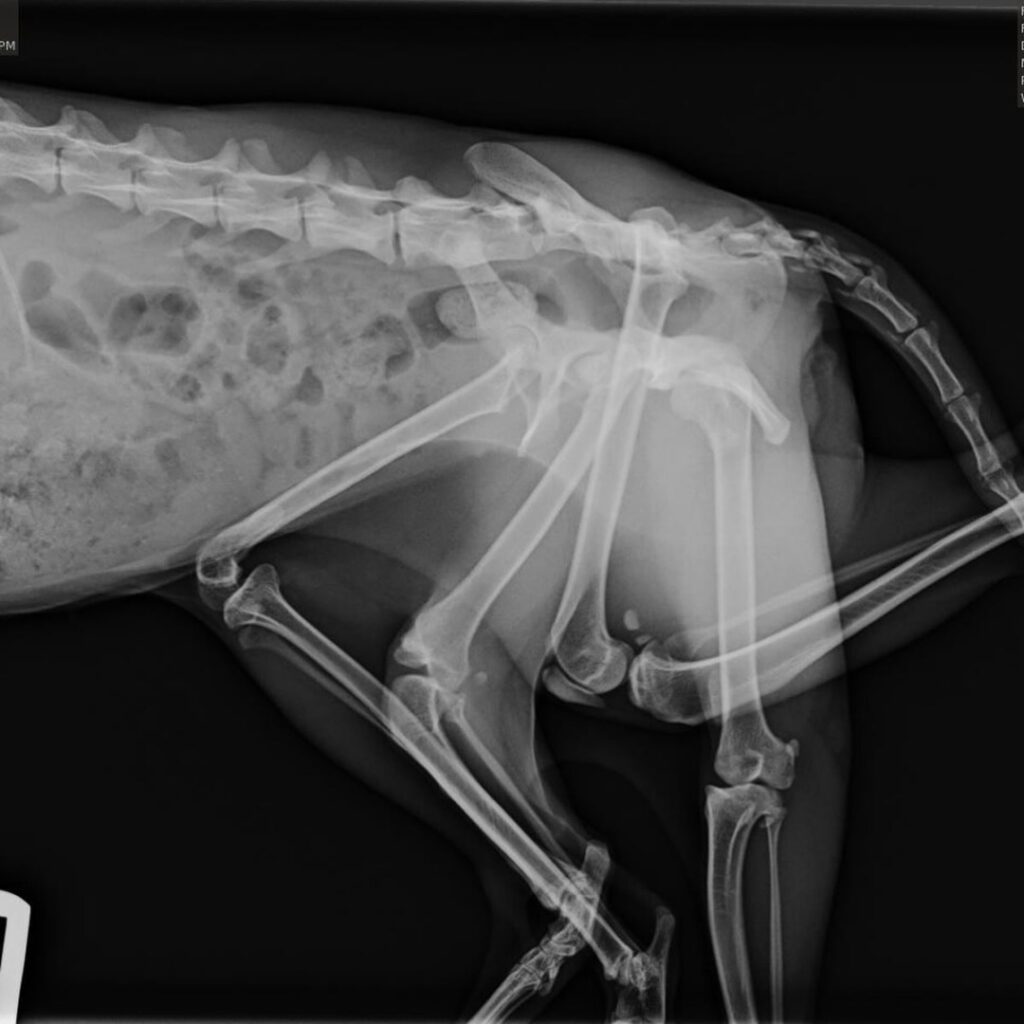

Bitsy a fost zărită rătăcind într-o curte, arătând speriată și plină de răni. Salvatorii au crezut inițial că poartă un pui pe spate sau suferă de o tumoră. Însă, realitatea era cu mult mai bizară: pisica avea două picioare în plus care îi creșteau dintr-o parte.

Potrivit specialiștilor, această afecțiune rară apare atunci când un animal absoarbe un geamăn în pântece.

Cele două membre în plus nu erau doar inutile, ci îi provocau dureri cumplite. Pe lângă ele, Bitsy mai avea un picior răsucit, atașat de un pelvis secundar nefuncțional, care o făcea să se târască cu greu. Activități simple, cum ar fi să ajungă la bolul cu mâncare, deveniseră o luptă zilnică.

Veterinarii au decis să îi îndepărteze cele trei membre problematice pentru a-i oferi o șansă la o viață normală. Operația de două ore a fost un succes total, iar Bitsy a avut o recuperare rapidă.